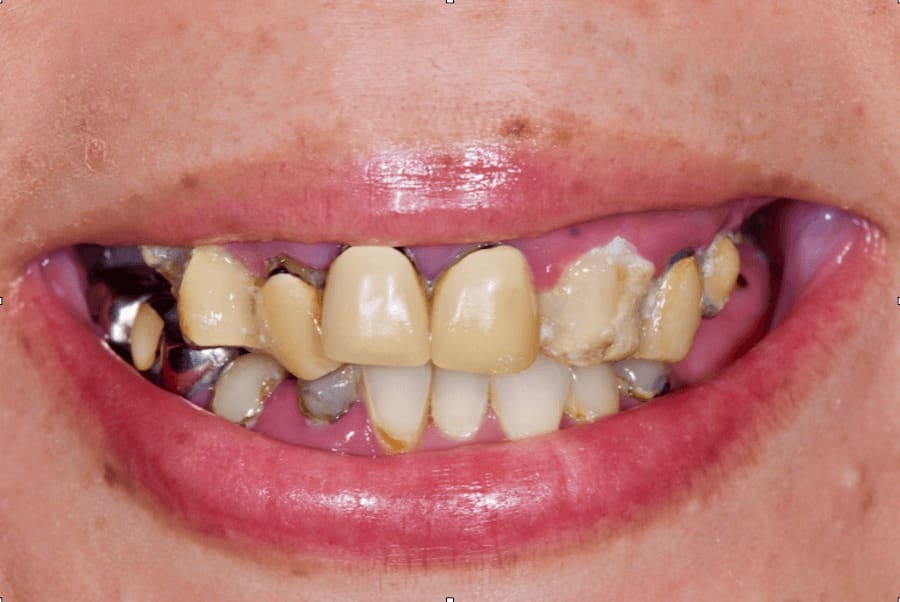

| お悩み | 歯がボロボロなのは分かっているが、時間的な余裕が無いことと歯科に対する恐怖心から、悪いままの状態を放置してしまった。人前でおもいっきり笑いたいので意を決して来院。 |

術前写真

上顎:

残せる歯はほとんど無い

下顎:

前歯のみ残せるが歯並びを改善する必要がある